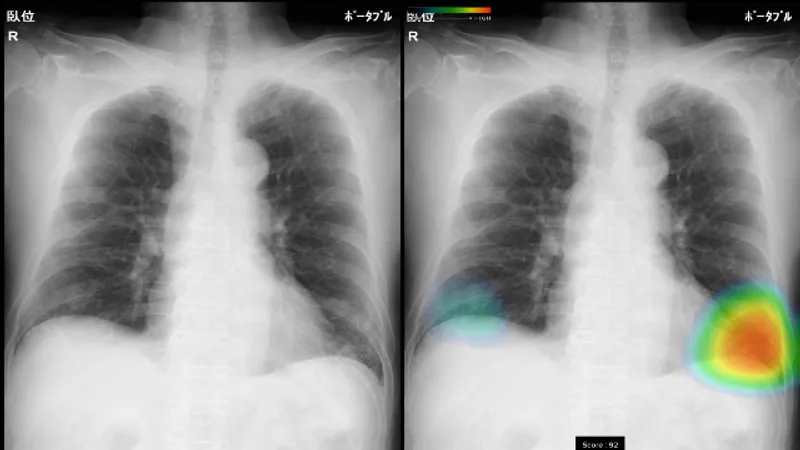

(1)ヒートマップ表示、スコア表示機能 結節・腫瘤影、浸潤影、気胸の候補領域を検出し、それらの異常領域の存在の可能性(確信度)を青から赤までのグラデーションカラーで表示します。確信度が低いほど青く、高いほど赤く表示します。また、各検出領域に対応する確信度の最大値をスコアで表示します。 (2)3つの画像所見に対応 本ソフトウェアの検出対象は、主要な肺疾患の画像所見である結節・腫瘤影、浸潤影、気胸の3所見です。健康診断や日常診療などにおけるさまざまな胸部疾患の診療に幅広く活用いただけます。